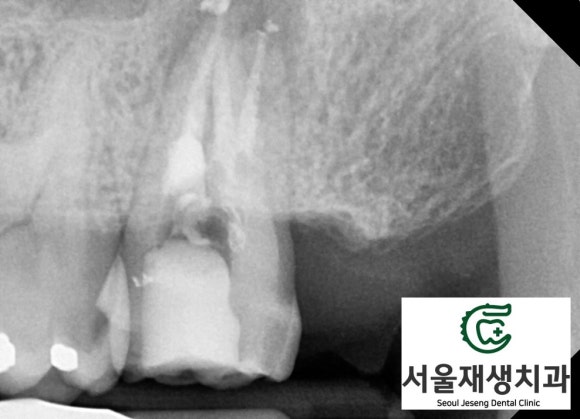

치아의 독사진을 촬영해봅니다.

단체사진보다 더 풍부하고 디테일한 정보를 줍니다.

일견 잘 되어 있는 치료처럼 보이지만,

밀도가 깊이가 부족해보입니다.

치아 내의 신경조직 잔사가 남아서 염증을 일으킨 것으로 보입니다.